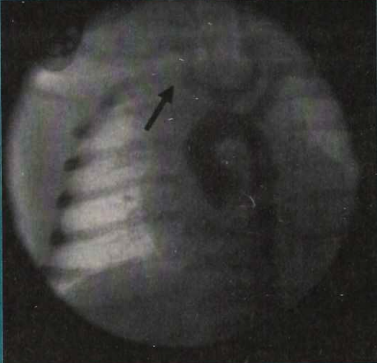

Case 3. A 6-month-old baby boy with a history of Ebstein’s anomaly had a right-to-left shunt across a large atrial septal defect. While in the intensive care unit, he presented with sudden-onset of diminished pulses in the right hand. The hand became pale and the patient was in obvious discomfort. However, after over 24 hours of intravenous heparin sulfate, there was no improvement of the hand. His hand color changed from pale to cyanotic and digital ulcerations were already apparent. Angiography revealed total occlusion of the right ulnar and radial arteries. We felt that the reason for this occlusion was an embolism. Tissue-plasminogen activator (t-PA) was administered, however, there was no improvement in blood flow after sufficient monitoring, thus PAT was performed.

Case 5. A 1-year-old with a neuromuscular disorder presented with a diminished pulse in the left hand and bluish discoloration of the 3rd, 4th, 5th fingertips. Arteriography was performed approximately 20 hours after the initial presentation and revealed occlusion of the left ulnar artery and obvious emboli to the digital arteries. The patient was treated with PT and t-PA. After 48 hours, the patient was brought back to the catheterization laboratory where a repeat arteriogram revealed stenosis of the ulnar artery at the level of the elbow and some residual thrombus in the 5th finger. The clot was removed and angioplasty was carried out. Excellent flow was observed upon completion of the procedure.